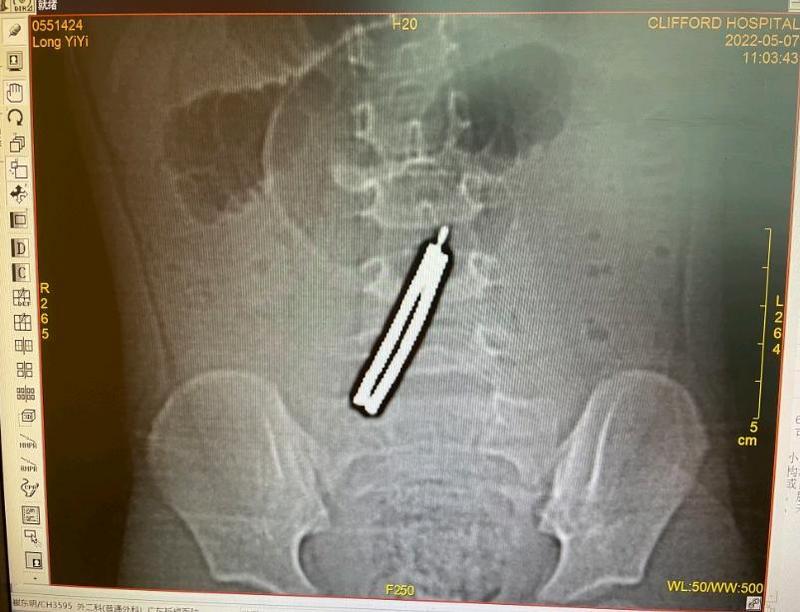

3岁女童误吞11块磁力棒,肠子磨穿5个洞

文/羊城晚报全媒体记者 陈辉 通讯员 戴敏图/受访者提供近日,3岁半的娜娜(化名)腹痛呕吐,还发高烧。日前,家人带着小孩来到广东祈福医院儿科就诊